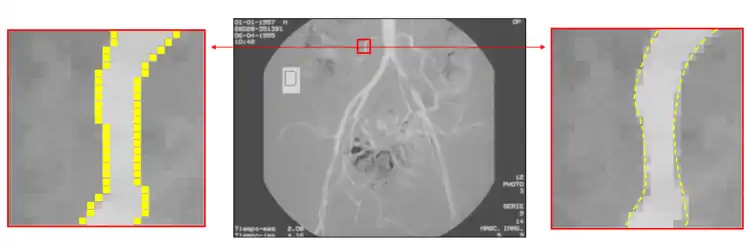

Subpixel